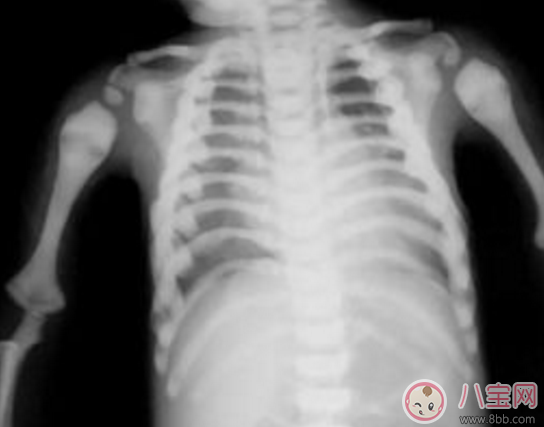

石骨癥又稱大理石骨病,是一種罕見的泛發性骨質硬化癥。特點是骨均勻硬化,骨小梁消失,骨脆弱,易骨折,白骨,為遺傳性疾病。由于骨髓發生硬化而導致貧血。該病為全身性疾病,多在兒童期被發現。病人矮小,骨正常結構消失,晚發性石骨癥病變進展緩慢,癥狀也輕,常因輕微外力就可導致骨折。

石骨癥病因不明,可能與遺傳因素有關。認為是由于正常的破骨細胞明顯缺乏或功能缺陷,主要變化為骨樣組織過度鈣化而缺少真正的骨化,使鈣化的軟骨基質及原始的骨小梁重吸收變慢,以致骨中缺少骨板層及成骨細胞,失去彈性,骨小梁結構不良,使骨質脆易斷。由于大量鈣化的軟骨基質的存在,使骨髓腔明顯縮小,甚至閉塞,骨皮質和松質硬化,二者之間不能分辨。骨皮質增生,骨松質致密而出現全身骨骼X線的特征性改變。